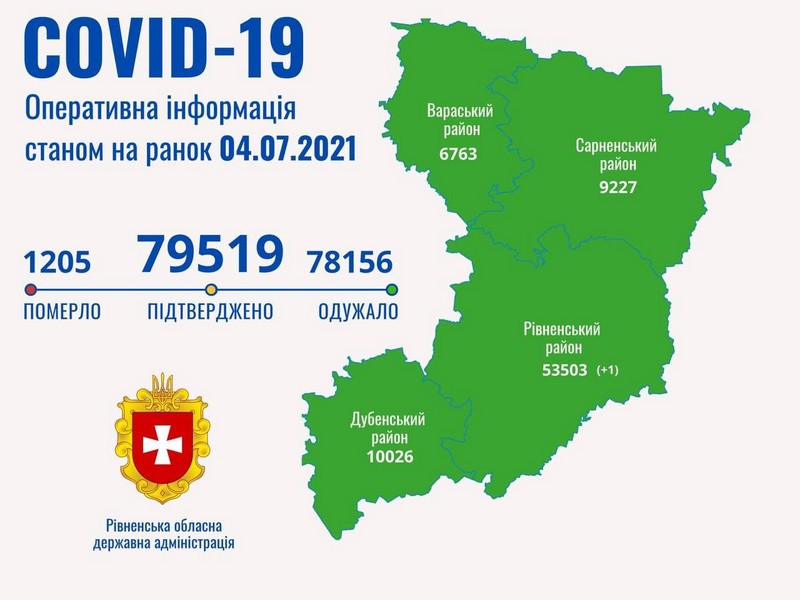

Коронавірус повертається: як стрімко зростає кількість хворих на Рівненщині (ВІДЕО)

Пів тисячі - у важкому стані, 9 жителів Рівненщини померли за добу від коронавірусу